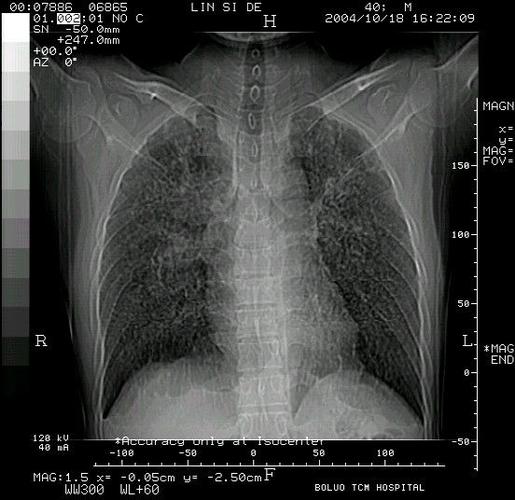

矽肺影像

矽肺影像,矽肺影像图片

矽肺

矽肺影像图片

矽肺胸片

矽肺x光

矽肺图片

矽肺病

矽肺三期

矽肺病图片

一期矽肺图片

正常胸片影像图片